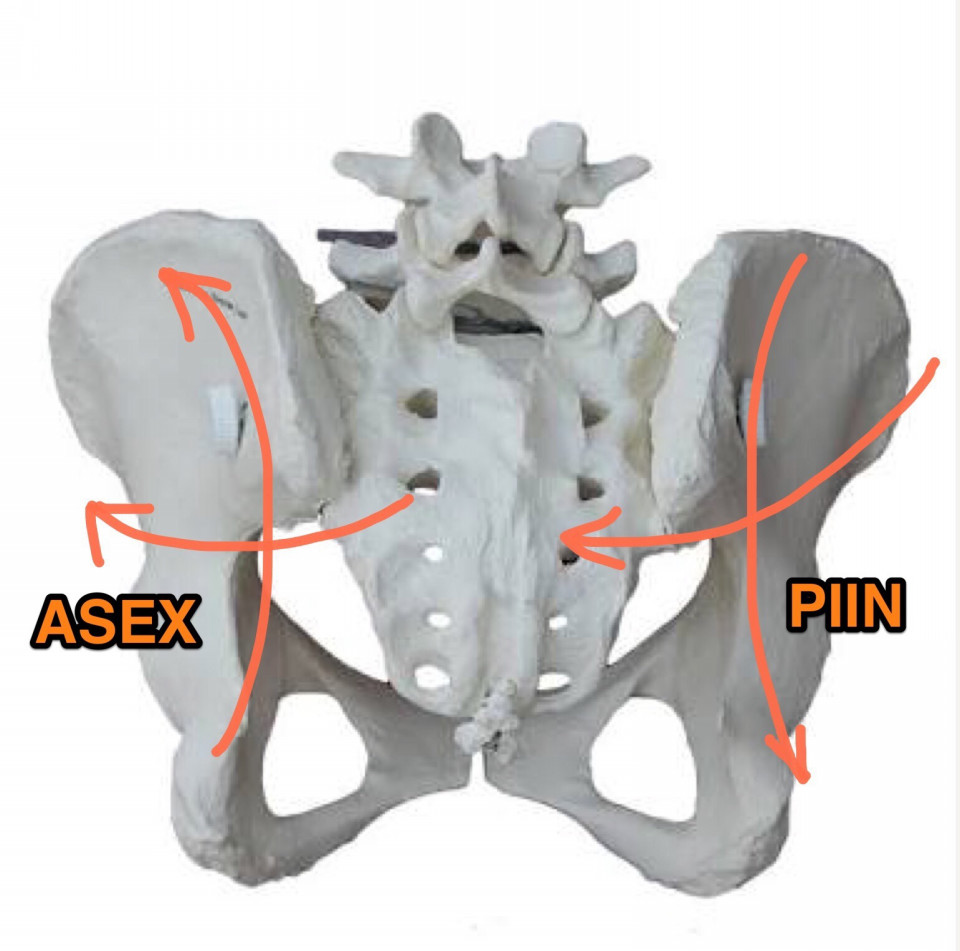

Ilium Misalignments - 骨盤の歪み方

Ilium Misalignments - 骨盤の歪み方

骨盤の触診 - PI/ASリスティングの場合

骨盤の触診 - PI/ASリスティングの場合

骨盤の触診 - EX/INリスティングの場合

骨盤の触診 - EX/INリスティングの場合

左右の骨盤の動き

左右の骨盤の動き